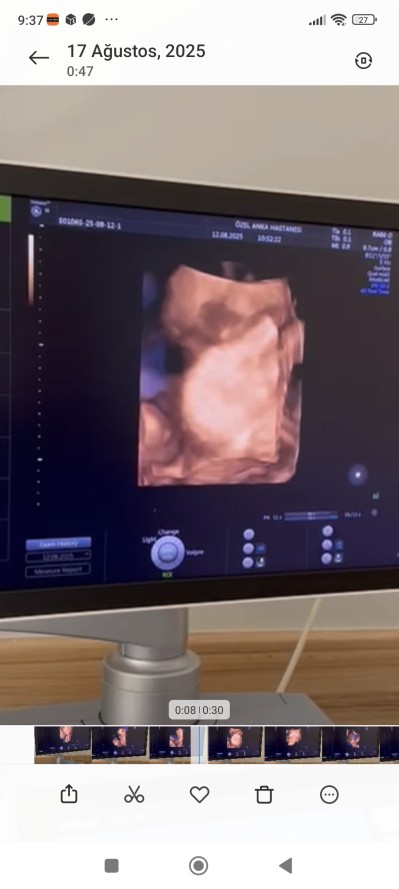

kizlar sizce o bacak arasındaki pipimi kordonmu

Gebelik haftası 26